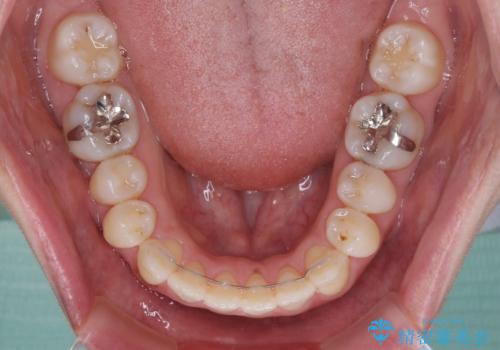

インビザラインによる矯正治療は、受け口傾向の治療に非常に適した方法であり、事前にシミュレーションに沿って治療を進めることできます。

今回の治療では骨格的な偏位があったためアンカースクリューを使用し、より確率の高い治療を行うことができました。